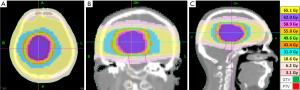

The patient was immobilized with a head rest, custom thermoplastic mask and underwent 3 mm sliced CT scan with contrast enhancement for simulation. The gross tumour volume (GTV) was contoured and a 3 mm margin was added to create planning target volume (PTV). The patient received radiotherapy using Helical TomoTherapy® (Accuray Incorporated, Sunnyvale, CA, USA). TomoTherapy® uses a fan-beam delivery system to deliver rotational intensity-modulated radiation therapy. The course of fractionated radiotherapy consisted of 62 Gy/31 fractions given 5 days per week of a period of 7 weeks. The brainstem was limited to less than 55 Gy and optic chiasm, lens, and optic nerves were also contoured with constrains to fulfill current standards for organ at risks. Ninety-eight percent of the PTV was covered by 62 Gy isodose curve line, and total GTV was covered 100% (Figure 3). The dose-volume histogram and dose to the region of interest (ROI) were illustrated in Figure 4. The patient received the radiotherapy uneventfully and the slurred speech recovered after the treatment. The acute side effect of the treatment was mild headache only. No other neurological sequelae developed during or after the treatment. The patient maintained his previous Karnofsky and ECOG scores, 90 and 1, respectively.

In our case, only biopsy was performed before EBRT due to the location of the tumor and to the tight adhesion of the adjacent structure. SRS was not suitable for this case since the maximal diameter of the tumor prior to treatment was 53 mm. Therefore, EBRT was chosen as the treatment technique. The tumor was contoured based on 3 mm CT simulation images with contrast enhancement. A 3 mm margin was added to the GTV to create PTV. The dose to PTV was 62 Gy in 31 fractions. Here we chose a higher prescribed dose with a smaller PTV according to the literature reviewed. The earliest report from Brat et al. showed long term survival for two cases who received partial resection followed by EBRT, but the prescribed dose was not stated clearly (23). In GKRS series, a marginal dose of 10–12 Gy was often used after the biopsy to maintain a local control (20). Another case with a local control of 9 months received a boost of 54 Gy by EBRT after partial resection and GKRS (11 Gy marginally) (22). In another case, tumor recurrence was observed 7 months after partial resection and adjuvant EBRT of 54 Gy (24). It seemed reasonable for us that a higher dose was needed for this rare disease.

In general, a 1–2 cm margin is suggested outside of GTV to form a PTV for low-grade gliomas. Since our patient had only slurred speech before the radiotherapy, we wanted to maintain his neurological function as much as possible. To sum up, instead of treating the patient with 50–55 Gy with a 1–2 cm margin, we ended up treating him with 62 Gy with a 3 mm margin. The patient completed the treatment smoothly.